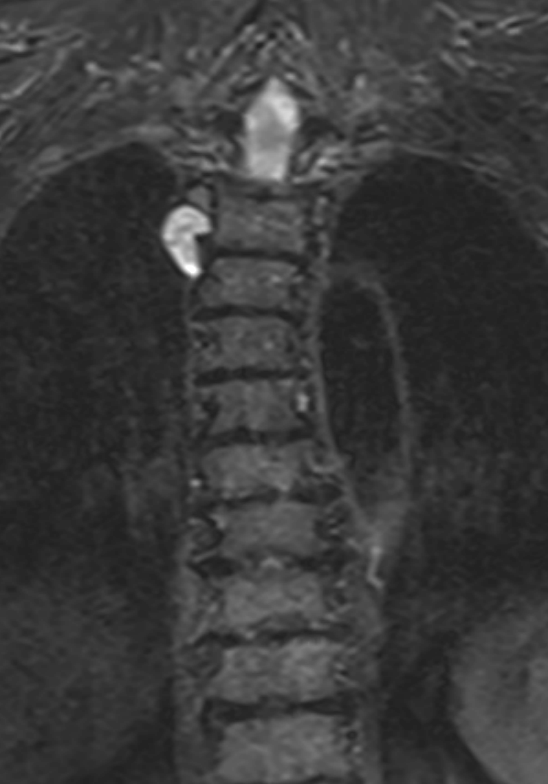

3. Peripheral nerve sheath tumour